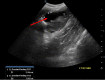

Vaginal agenesis is part of a group of anomalies, referred to as Mullerian anomalies due to their embryologic origin, in which there is a congenital absence of the vagina. We present a unique case in which a 20-year-old female presented to the Emergency Department with cyclical abdominal pain and primary amenorrhea. The original assessment showed a probable imperforate hymen; however, it was later found that she likely had vaginal agenesis. Vaginal agenesis is a rare disease, but it is prevalent enough that it should be kept at the forefront of the differential diagnosis in a woman with primary amenorrhea and recurring pain. We also highlight the importance of patient education in general, but categorically to sexual health.